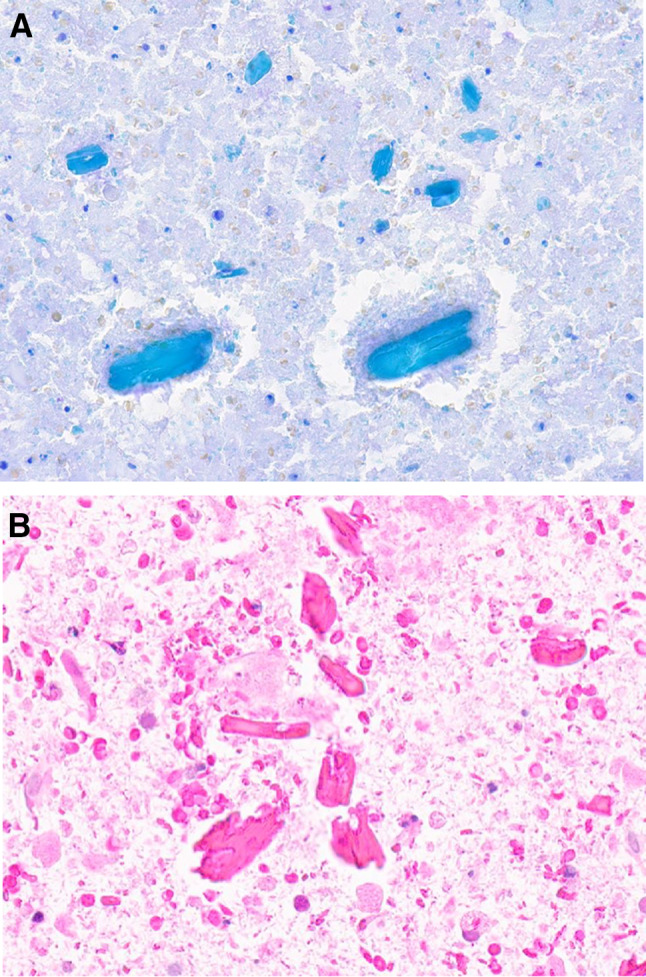

Fig. 12.

Amylase crystalloid granuloma. (Left) Inflammatory cyst associated with a marked peripheral foreign body reaction to crystalloids (H&E stain, magnification × 10). (Right) Numerous eosinophilic amylase crystalloids are shown mixed with histiocytes and multinucleated giant cells (H&E stain, magnification × 40)